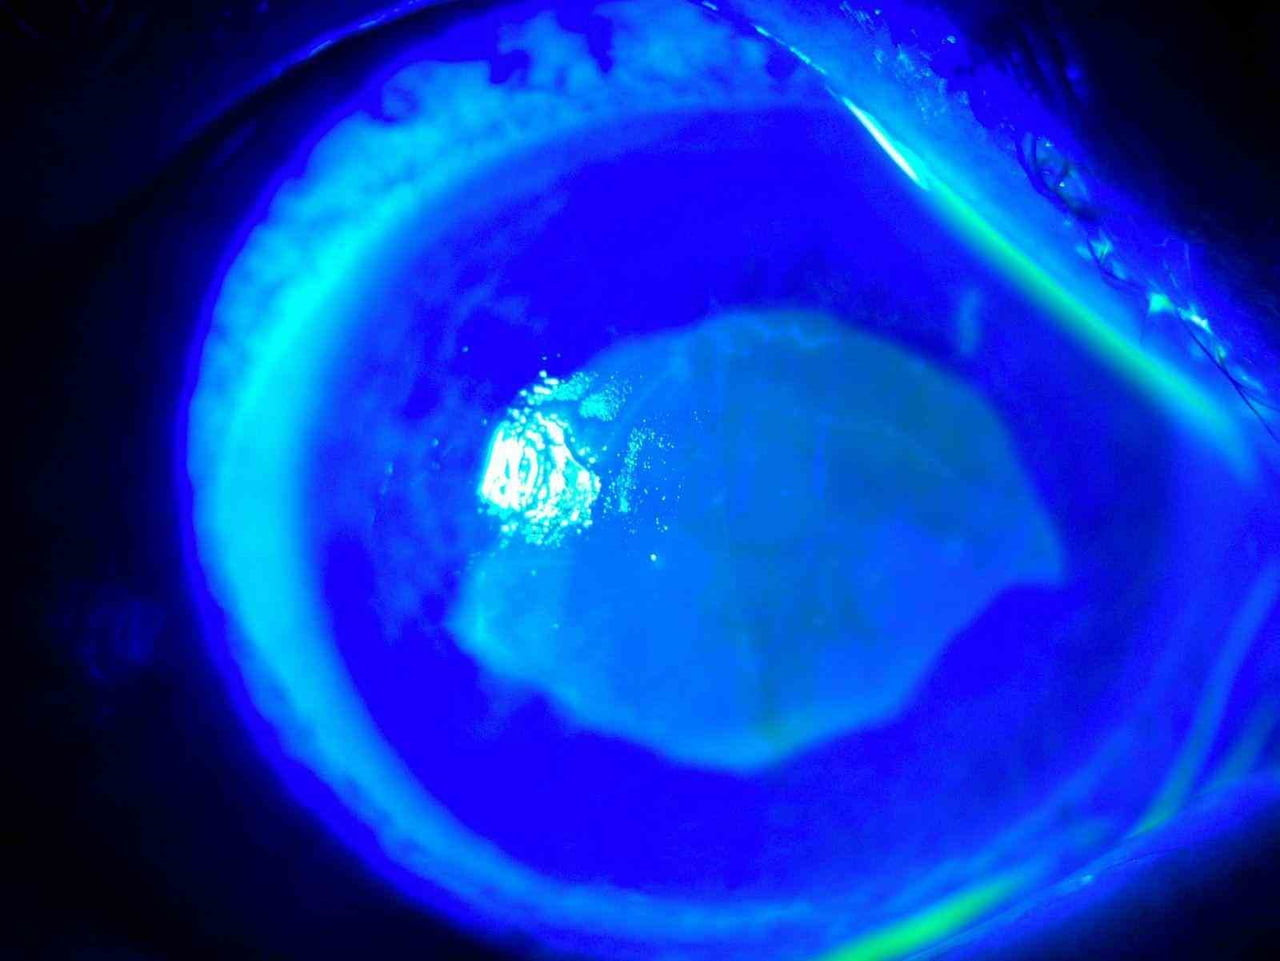

Göz Hastalıkları Uzmanı Doç. Dr. Ömer Faruk Yılmaz, "Hastamız, kırlangıç otu suyunu damlattıktan sonra gözlerini açamaz hale geldi. Görüş alanı tamamen kayboldu ve kornealarında ciddi tahribat meydana geldi" dedi. Hastanın tedavi sürecine dair bilgi veren Yılmaz, doğru tedavi ile hastanın sağlığına kavuştuğunu belirtti.

Hastanın göz muayenesinde kornea epitelinin tahrip olduğu belirlendi ve hızlı bir tedavi süreci başlatıldı. Yılmaz, "Tedavi sürecimiz yaklaşık 2 hafta sürdü ve sonunda hastamız tamamen iyileşti" diye ekledi.